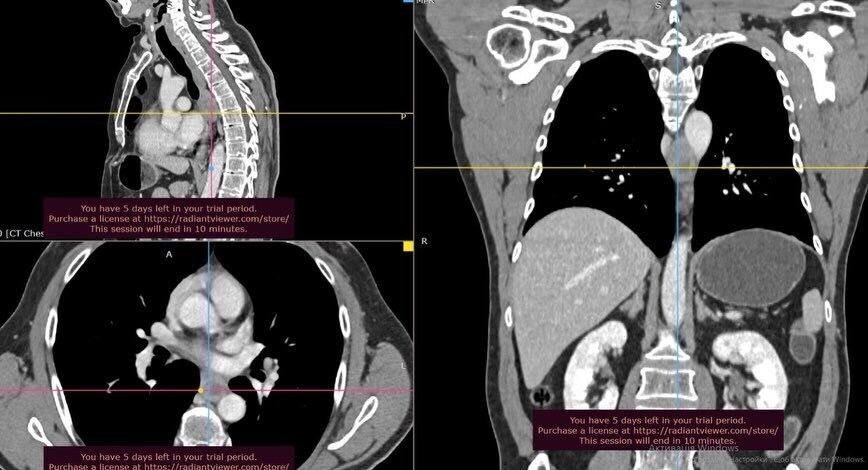

Серед прооперованих пацієнтів була людина зі злоякісною пухлиною діафрагми, яка вже почала поширюватися на стінку серцевої сумки. Іншим складним випадком стала стромальна гастроінтестинальна пухлина стравоходу. Вона розташовувалася у вкрай небезпечній анатомічній зоні — між стравоходом та низхідною аортою, що спричиняло серйозні порушення ковтання. Третім пацієнтом став молодий чоловік із великою тератомою лівого піддіафрагмального простору. Пухлина, яку спостерігали понад три роки, значно змістила прилеглі органи.

Усі операції медики виконали малоінвазивним шляхом. Використання сучасної високоточної апаратури дозволило радикально видалити пухлини, зберігши при цьому функції органів. Такий підхід забезпечує пацієнтам значно швидше відновлення після втручання порівняно з традиційними методами.